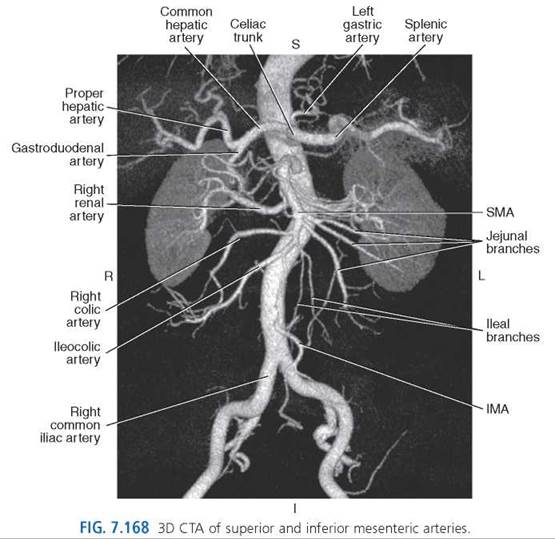

Celiac Trunk. The celiac trunk is a very short vessel that leaves the anterior wall of the aorta just after the aorta passes through the diaphragm. The short celiac trunk divides into three branches: left gastric, common hepatic, and splenic arteries (Figs. 7.151-7.153). Variations of the celiac trunk are not rare; occasionally, the common hepatic artery will branch directly from the superior mesenteric artery.

The left gastric artery courses superiorly and toward the left within the lesser omentum to supply the cardiac region of the stomach, then passes along the lesser curvature toward the pylorus, giving off esophageal and gastric branches to supply the abdominal esophagus and adjacent anterior and posterior walls of the body of the stomach. The left gastric artery continues toward the right to anastomose with the right gastric artery (Figs. 7.151, 7.154, 7.155, and 7.157).

The common hepatic artery crosses to the right toward the superior aspect of the duodenum and divides into the proper hepatic artery and the gastroduodenal artery (Figs. 7.151-7.153, 7.156, and 7.157). The proper hepatic artery ascends obliquely to the right in the hepatoduodenal ligament, adjacent to the portal vein and CBD, divides near the porta hepatis into the right and left hepatic branches, and usually gives off the right gastric artery (Figs. 7.151, 7.156, and 7.157). The right hepatic branch dispatches the cystic artery to the gallbladder and divides into the anterior and posterior segmental arteries to supply the segments of the right and caudate lobes of the liver. The left hepatic branch also gives off an artery to the caudate lobe, as well as medial and lateral segmental arteries to supply the segments of the left lobe and the intermediate branch to the quadrate lobe. The right gastric artery, which can also arise from the common hepatic or gastroduodenal arteries, supplies the lower part of the lesser curvature of the stomach and anastomoses with the left gastric artery within the lesser curvature of the stomach (Figs. 7.151 and 7.157). The gastroduodenal artery descends behind the pylorus to give off many branches, including the anterior and posterior superior pancreaticoduodenal arteries, which supply the superior part of the duodenum and head of the pancreas, and the right gastroepiploic (gastro-omental) artery. The right gastroepiploic artery passes through the greater omentum, anastomoses with the left gastroepiploic artery on the inferior surface of the greater curvature, and dispatches numerous gastric branches to the anterior and posterior walls of the pyloric and body portions of the stomach (Figs. 7.151 and 7.156-7.158).

The splenic (lienal) artery is the largest branch of the celiac trunk and passes to the left behind the stomach and along the upper border of the pancreas, within the splenorenal ligament, to the hilum of the spleen. At the point where the splenic artery courses near the border of the pancreas, it gives off numerous pancreatic branches including the dorsal, great, and caudal pancreatic arteries that supply the body and tail of the pancreas (Fig. 7.159). Just before the splenic artery terminates into numerous splenic branches, it gives rise to the left gastroepiploic (gastro-omental) artery, which gives off epiploic and gastric branches to the greater omentum and anterior and posterior walls of the fundus of the stomach (Figs. 7.151 and 7.156-7.161).

Superior Mesenteric Artery. The large superior mesenteric artery (SMA) emerges just below the celiac trunk at approximately the level of L1 (Figs. 7.139, 7.162, and 7.163). It descends behind the body of the pancreas, then over the horizontal portion of the duodenum to course in the mesentery to the ileum (Figs. 7.158, 7.162, and 7.164-7.167). The artery supplies the head of the pancreas and the majority of the small and large intestines. Branches of the superior mesenteric artery include the inferior pancreaticoduodenal artery, jejunal arteries, ileal arteries, middle colic artery, right colic artery, and ileocolic artery.

The inferior pancreaticoduodenal artery extends to the head of the pancreas and duodenum, and then divides into the posterior ramus, which anastomoses with the posterior superior pancreaticoduodenal artery, and the anterior ramus, which anastomoses with the anterior superior pancreaticoduodenal artery. The jejunal and ileal arteries extend to supply the jejunum and ileum, except the end segment near the cecum. The middle colic artery reaches the transverse colon, and the right colic artery passes to the ascending colon. The ileocolic artery courses behind the peritoneum across the right ureter into the right iliac fossa and divides to supply a portion of the ascending colon, cecum, vermiform appendix, and terminal portion of the ileum (Figs. 7.166 and 7.168).